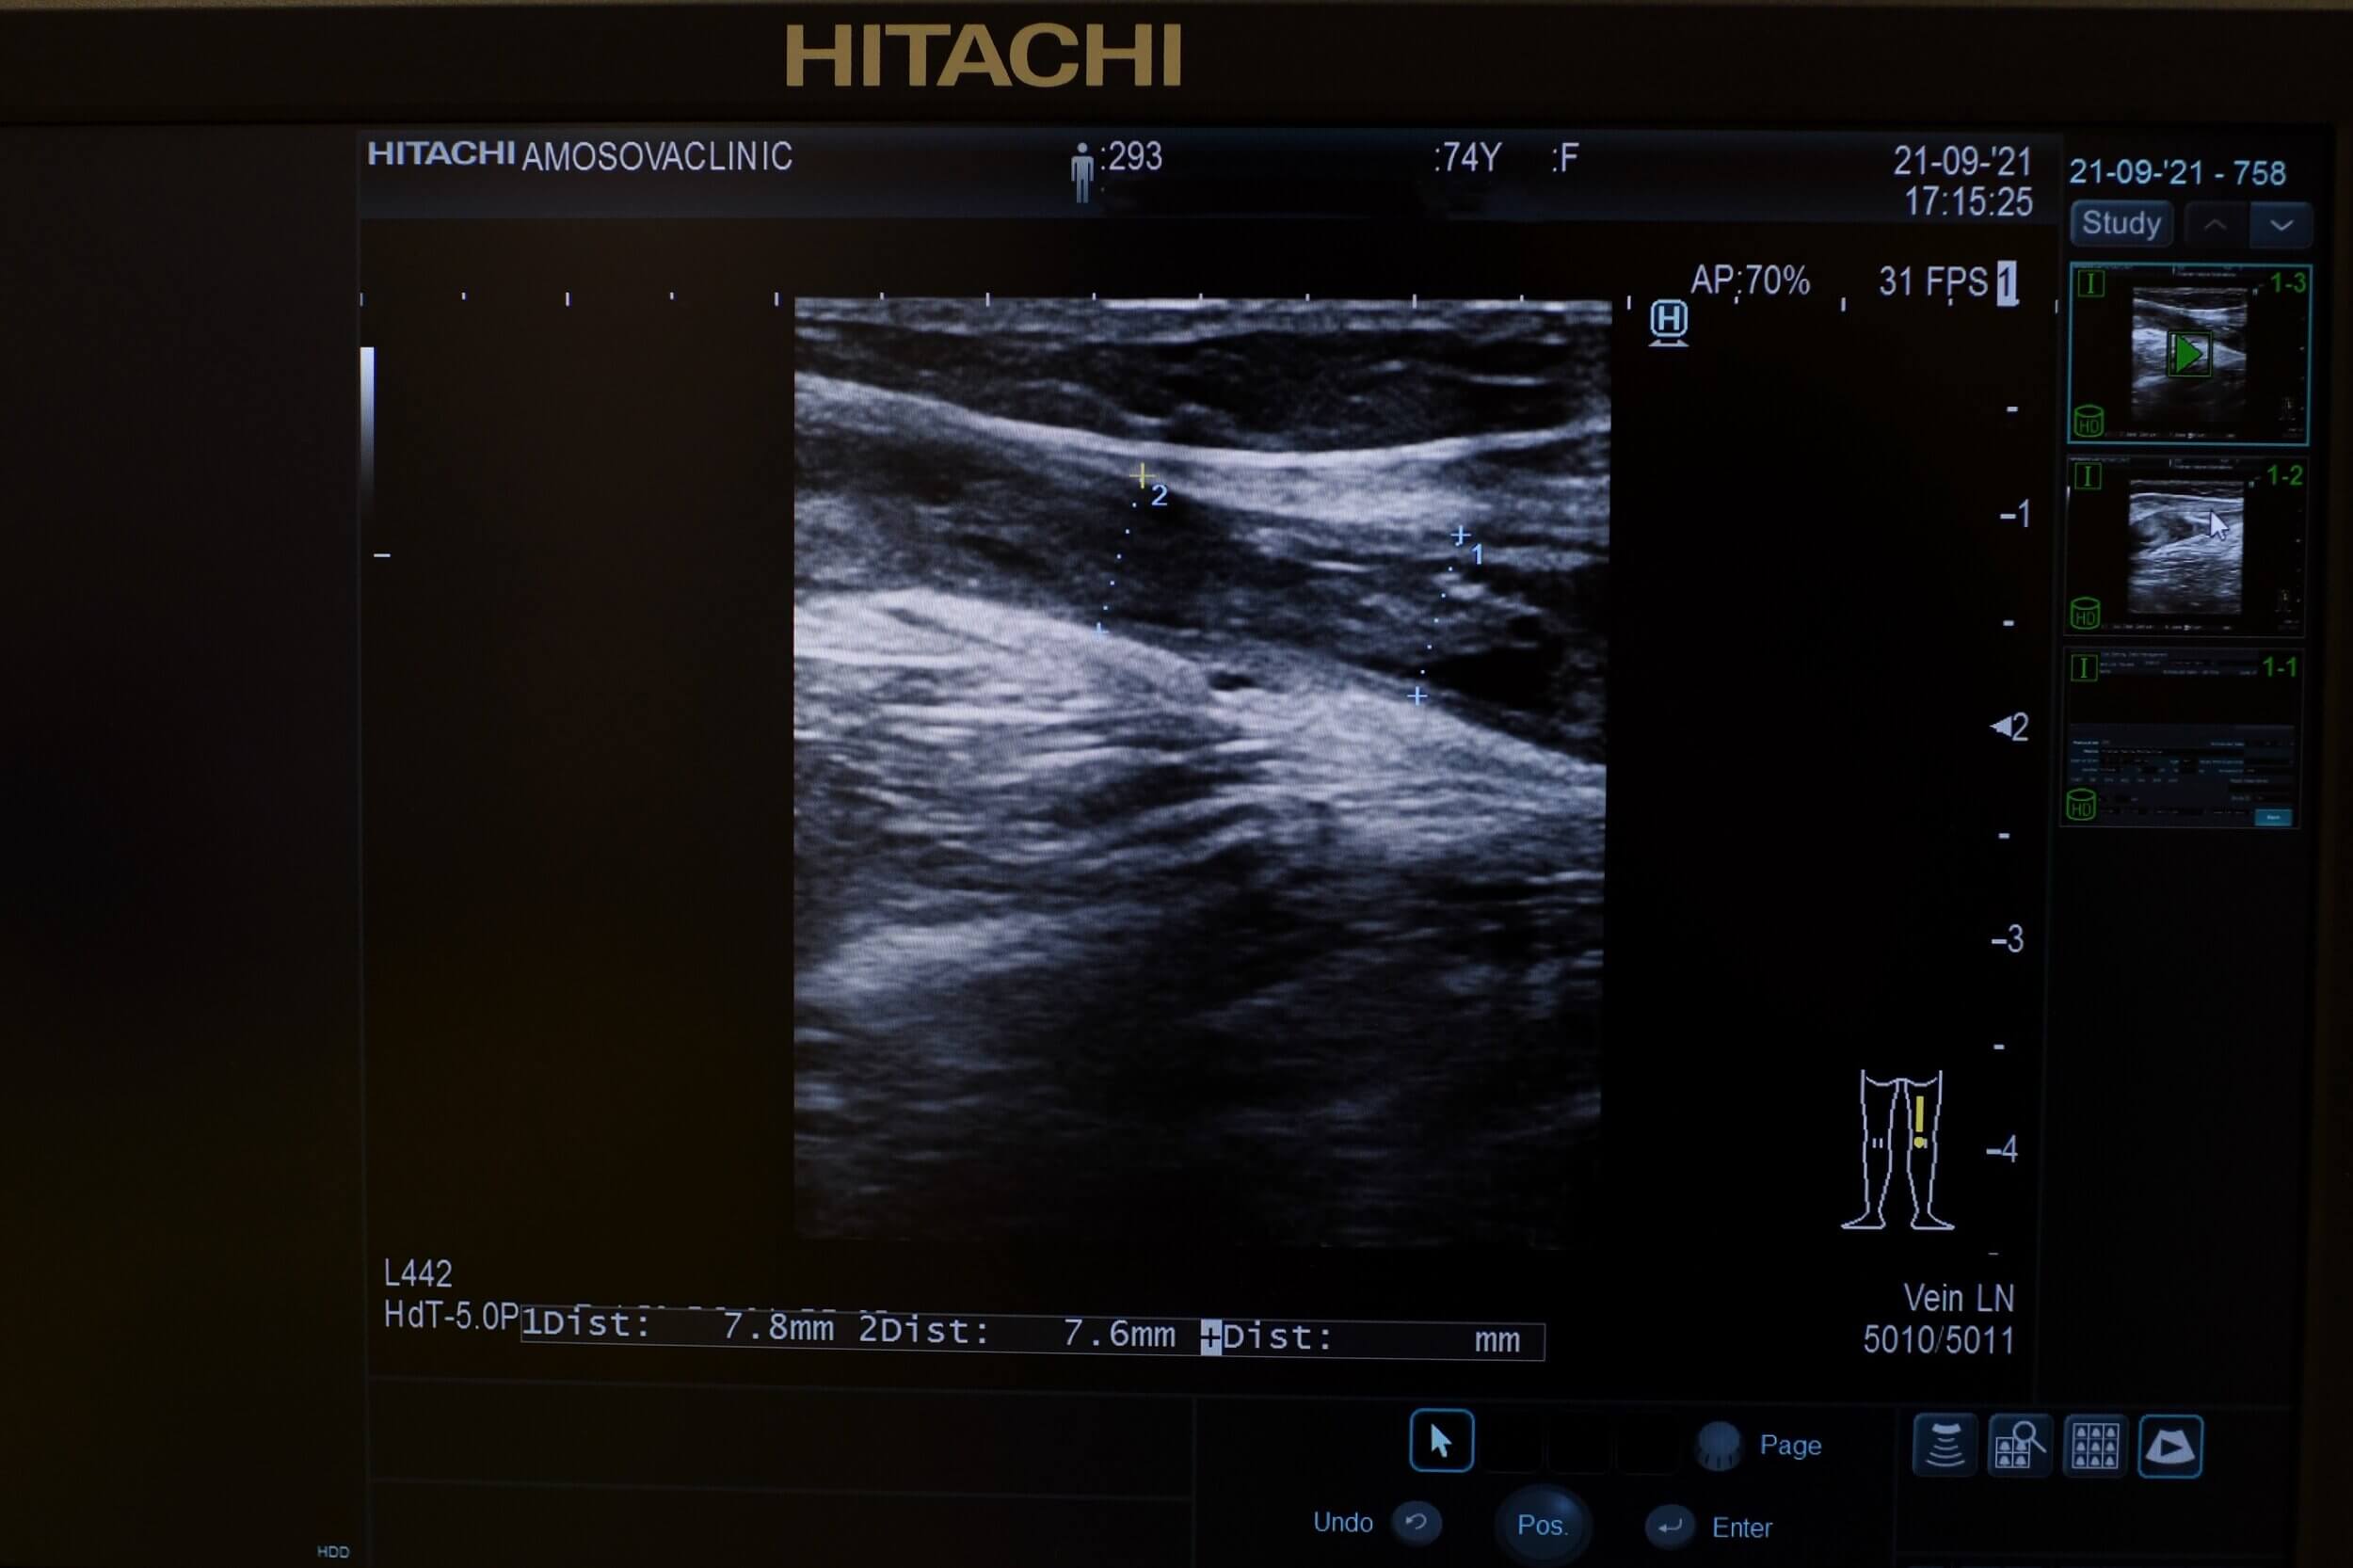

• доплер-УЗД артеріальних і венозних (поверхневих і глибоких) судин нижніх кінцівок, таза, черевної аорти та шиї,